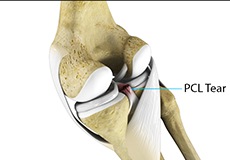

PCL Injuries

Posterior cruciate ligament (PCL), one of the four major ligaments of the knee, is situated at the back of the knee. It connects the thighbone (femur) to the shinbone (tibia). The PCL limits the backward motion of the shinbone.